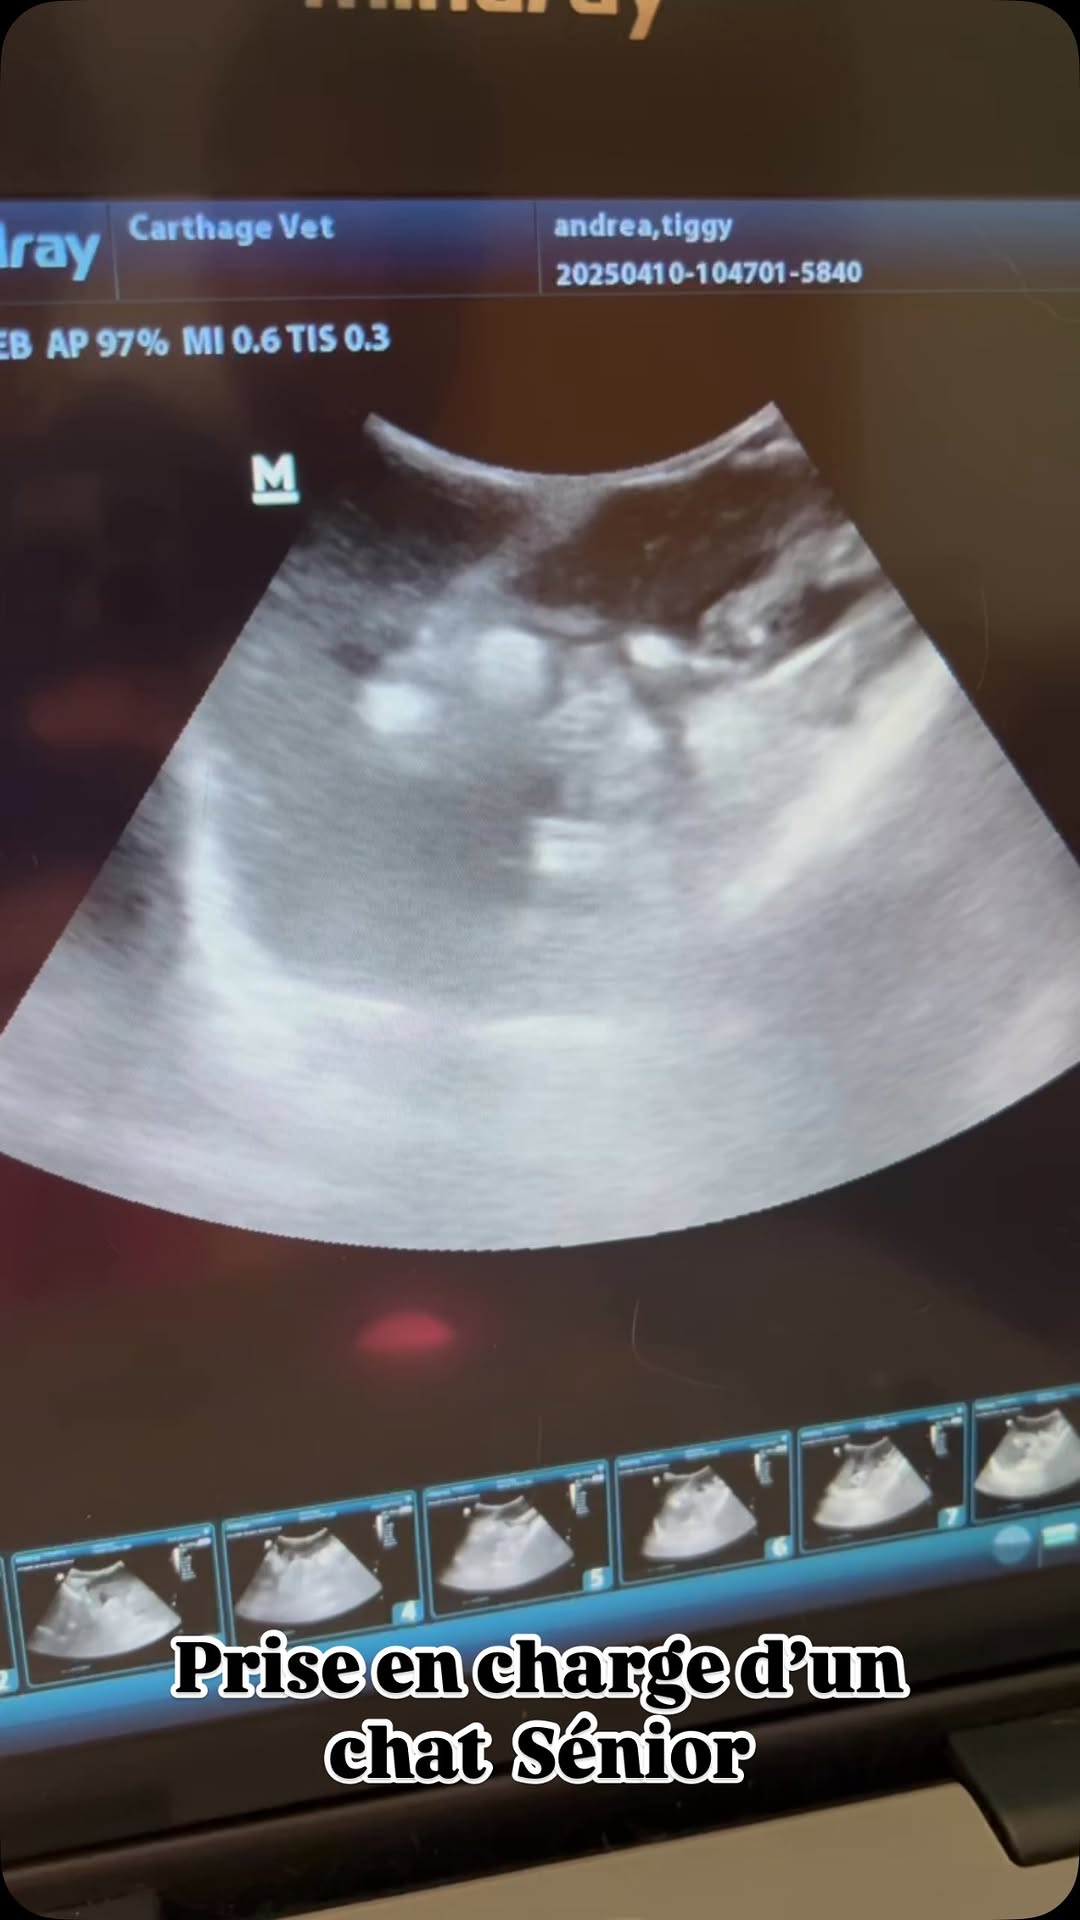

Aujourd’hui c’était le jour du bilan de santé de Tiggy, un chat 🐈‍⬛ sénior de 11 ans, qui a plusieurs problèmes de santé et qui nécessite un suivi régulier. 🩺

Au menu:

- bilan hépato-rénal complet 💉

- échographie abdominale 📟

- test rapide FelV-FIV-Corona 🩸

Si votre chat commence à prendre de l’âge, il est temps de prendre sa santé plus au sérieux. ⚠️ N’hésitez pas à demander conseil à votre vétérinaire 👩‍⚕️ qui saura effectuer les bilans nécessaires en fonction de son âge et de ses antécédents.